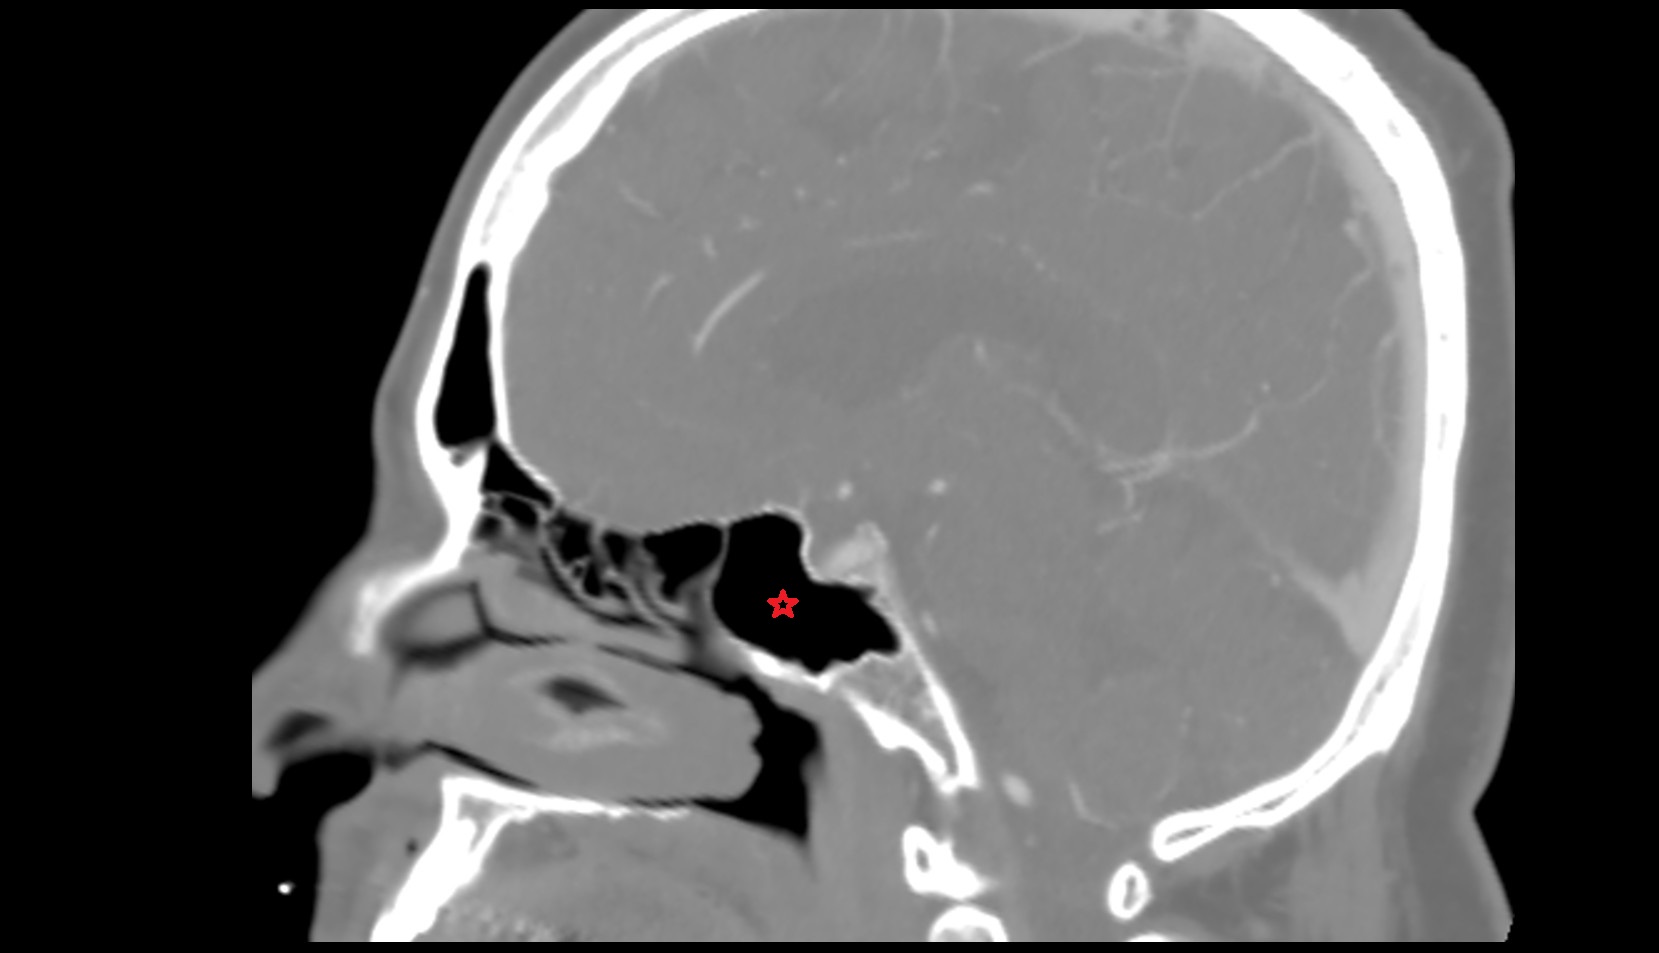

- Chiasmatic cistern